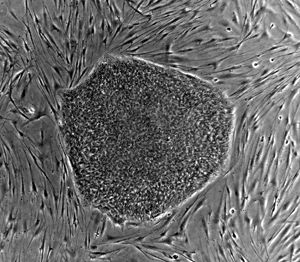

Nearly all research to date has taken place using mouse embryonic stem cells (mES) or human embryonic stem cells (hES). Both have the essential stem cell characteristics, yet they require very different environments in order to maintain an undifferentiated state. Mouse ES cells are grown on a layer of gelatin and require the presence of Leukemia Inhibitory Factor (LIF). Human ES cells are grown on a feeder layer of mouse embryonic fibroblasts (MEFs) and require the presence of basic Fibroblast Growth Factor (bFGF or FGF-2). Without optimal culture conditions or genetic manipulation, embryonic stem cells will rapidly differentiate.